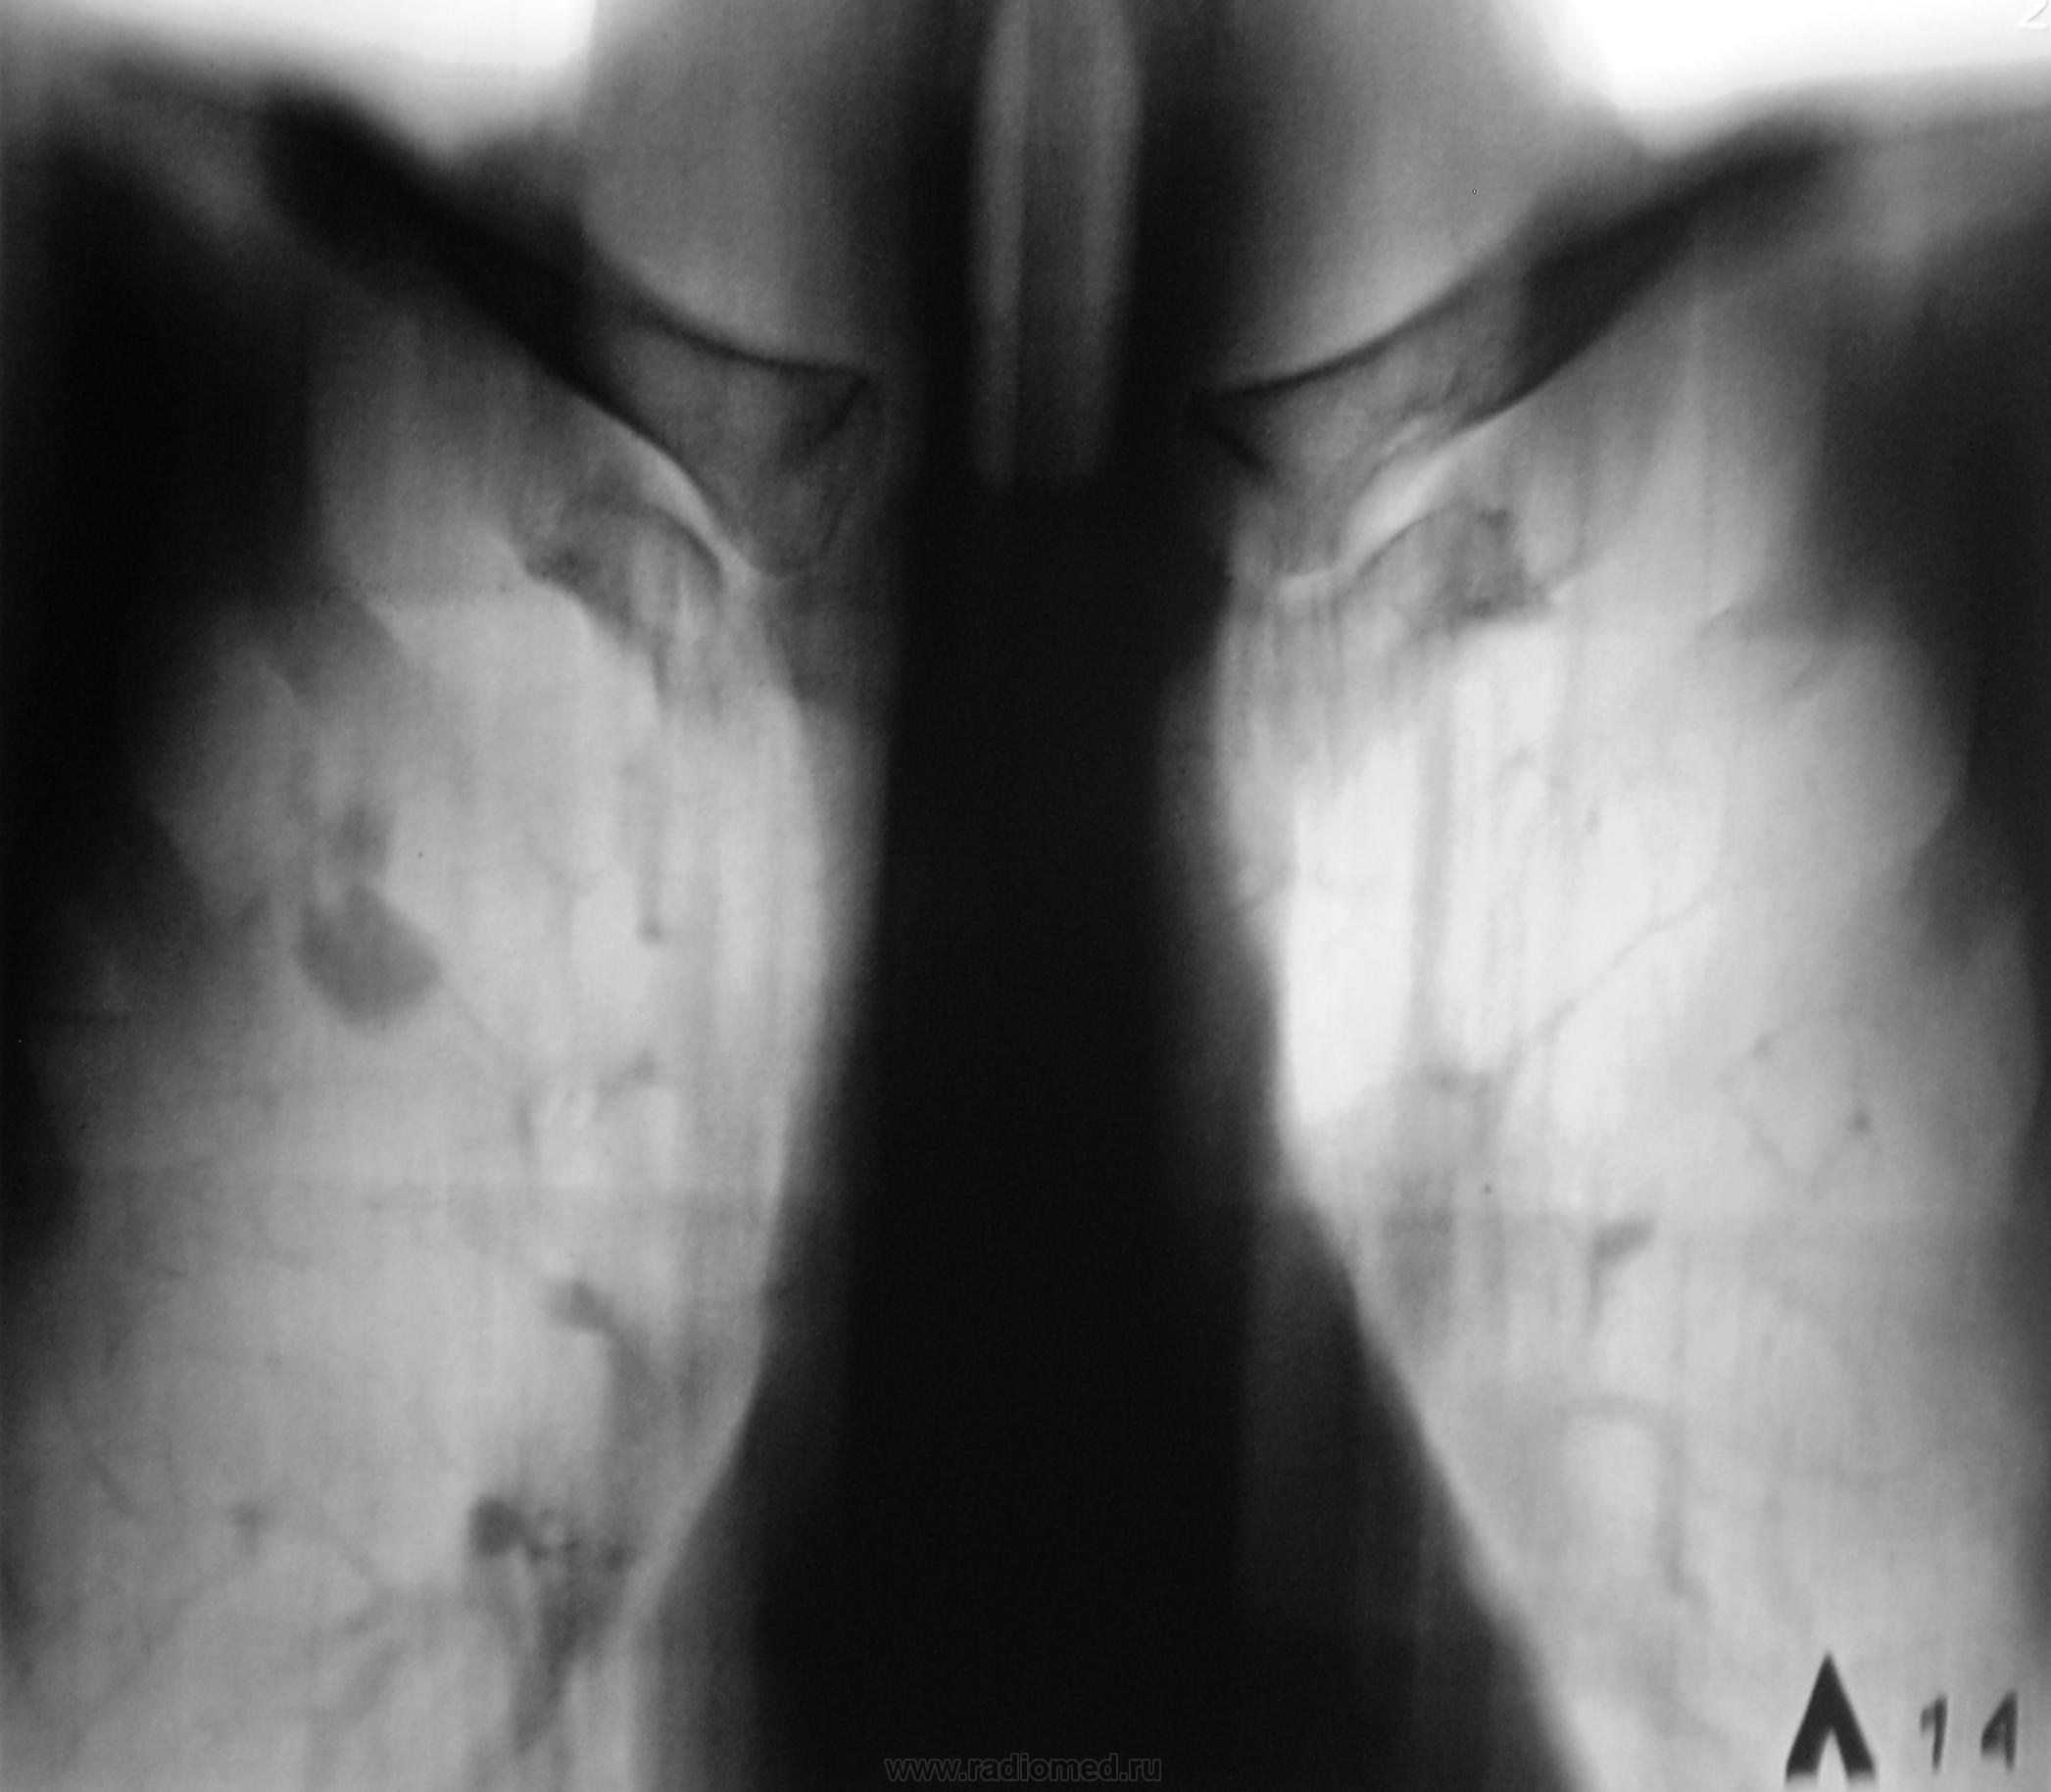

А, вчера был контроль после проведенного лечения, по поводу специфического процесса.

Приложения:

1.seg_.p1190038.jpg2.seg_.p1190039.jpg3.seg_.p1190039a.jpg4.seg_.p1190040.jpg5.seg_.p1190040a.jpg

В ОПТД (вторые снимки) был выставлен инфильтративный.